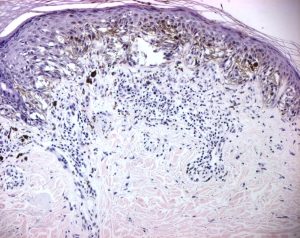

Esame istologico

Entrambe le lesioni sono state sottoposte ad asportazione chirurgica.

- Lesione addominale: melanoma a diffusione superficiale a cellule fusate, con discreta risalita intraepidermica (Melanoma Livello II, 0,7 mm secondo Breslow).

- Lesione del braccio sinistro: melanoma in fase verticale di invasione (Melanoma Livello III, 2,2 mm secondo Breslow).